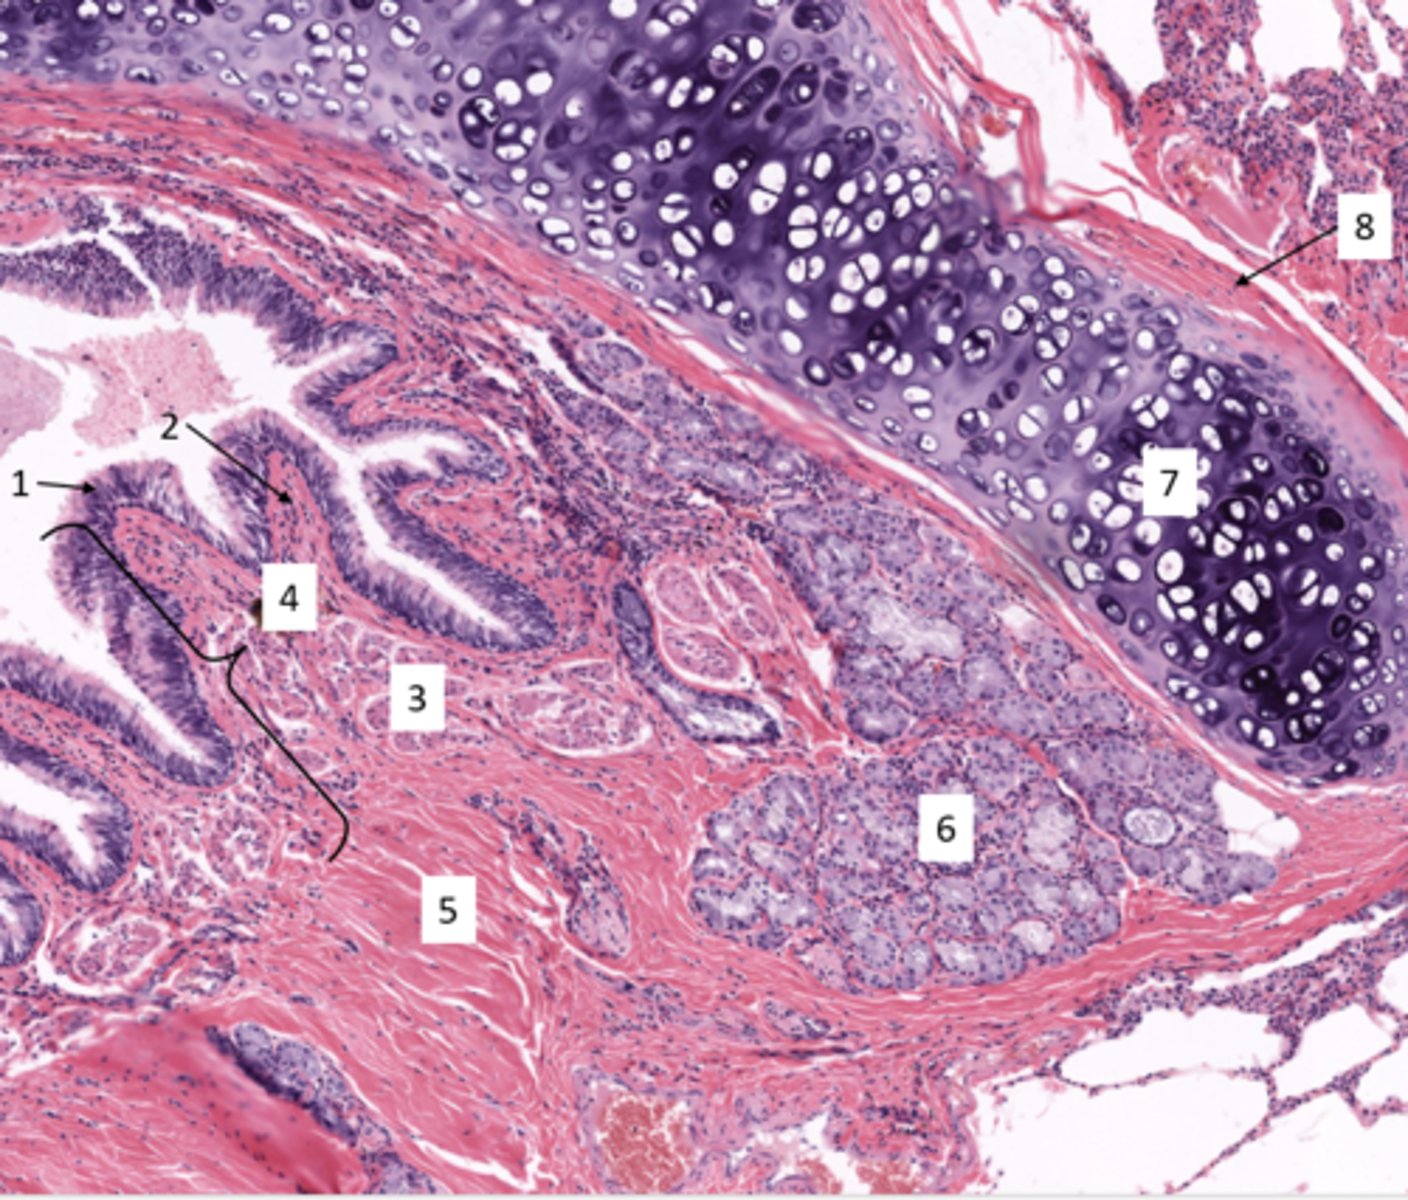

Identify the duct in cross section of the urinary system

ureter

Identify the layer of the ureter

transitional epithelium

lamina propria

Identify the layer of the bladder at 4

smooth muscular wall